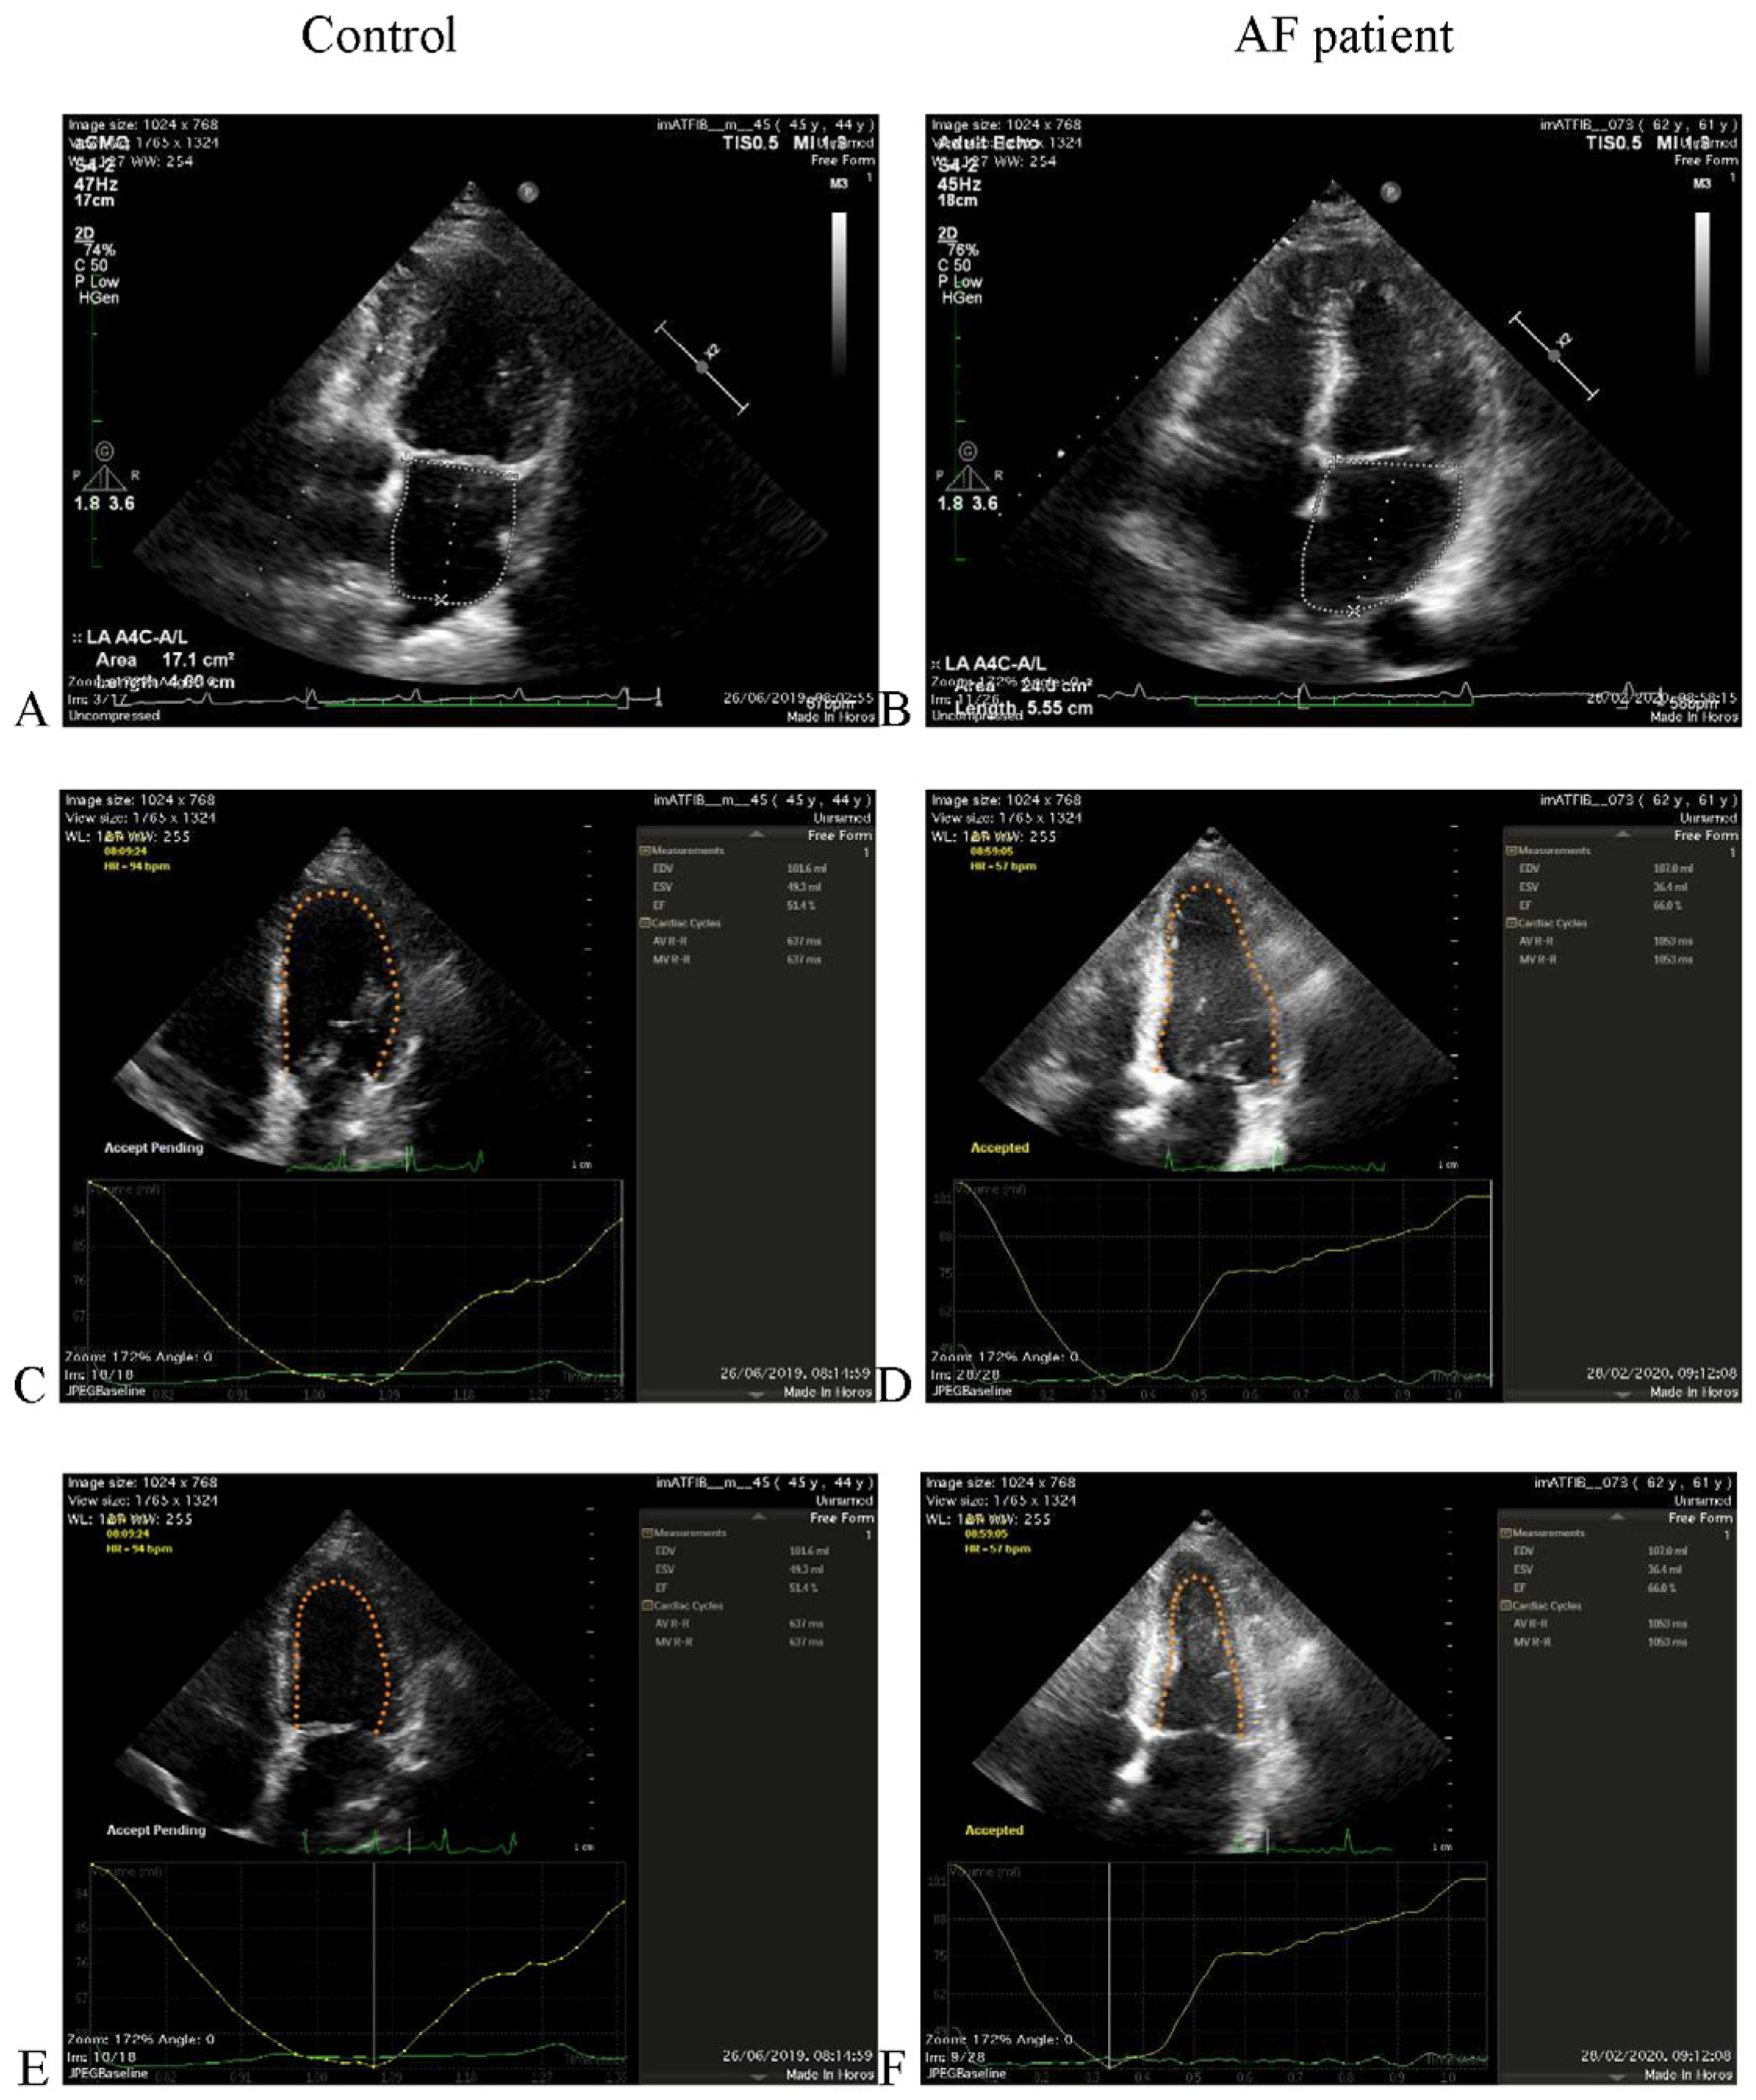

2.1. Echocardiographic Acquisition

| LA Vol (mL) | |||

| All | 86.8 (64.75–110.0) | 85.3 (62.4–113.8) | 0.54 |

| Controls | 64.3 (52.0–75.63) | 57.5 (46.7–68.8) | 0.085 |

| AF patients | 99.9 (81.05–124.6) | 104.8 (83.8–132.0) | 0.81 |